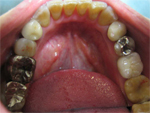

インプラント

インプラント治療の症例写真

上顎8本欠損症例

術前

術後